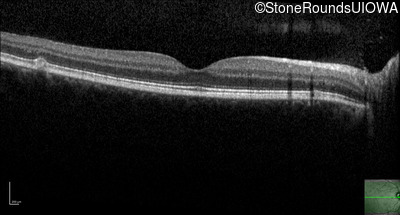

AR Stargardt Disease (IIA)

Age at visit: 30 years

This 30 year old asymptomatic man had fundus abnormalities identified incidentally on a routine exam.

Diagnosis & molecular findings

Disease Gene Allele 1 variant(s) Allele 2 variant(s) Inheritance mode

AR Stargardt Disease ABCA4 IVS30+1321 A>G Asn965Ser AAT>AGT AR